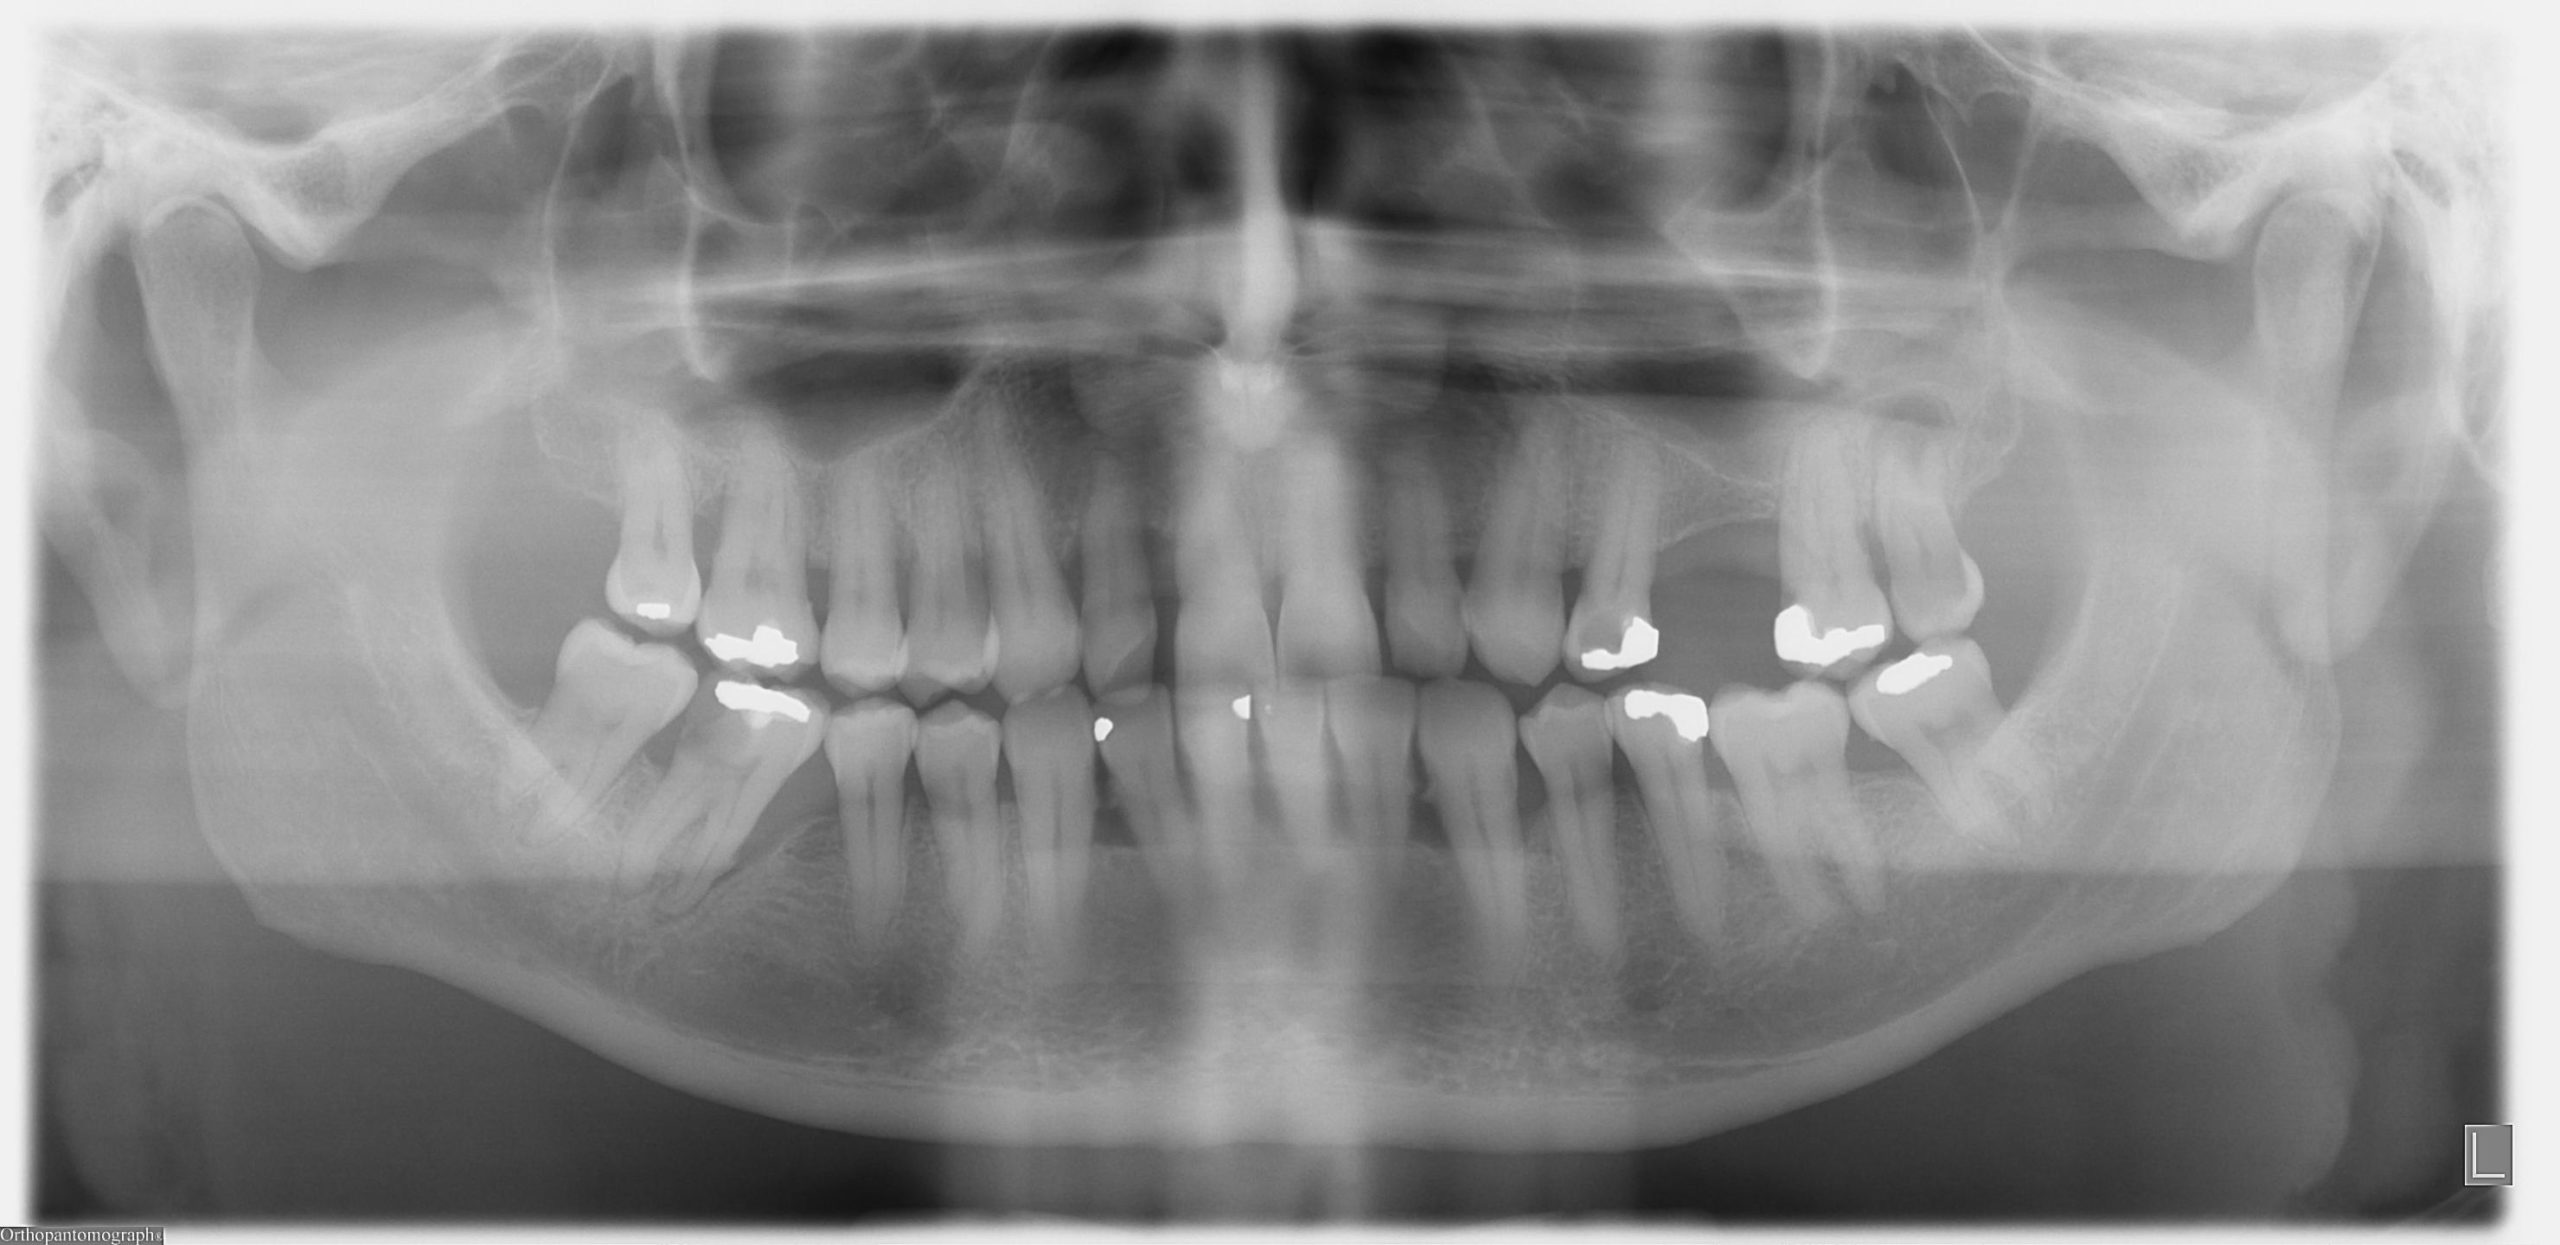

While most cases of childhood halitosis can be resolved with improved hydration and better brushing habits, there are times when the odor signals a need for professional help. If you have diligently cleaned the teeth, scraped the tongue, and ensured your child is well-hydrated, yet the smell persists, it is time to look deeper. Chronic bad breath can be a sign of dental decay that is not visible to the naked eye, such as cavities between teeth or infections under the gum line. A pediatric dentist has the tools to spot these hidden issues before they become painful emergencies.

Furthermore, the issue might be related to the airway. Enlarged tonsils or adenoids can trap food particles and bacteria, creating "tonsil stones" that smell terrible. They can also force a child to breathe through their mouth exclusively, perpetuating the dry mouth cycle. Additionally, digestive issues, such as acid reflux, can cause a sour odor that tooth brushing cannot mask. This is harmful not just for the smell, but because the acid can erode tooth enamel. Rather than guessing, viewing persistent bad breath as a diagnostic signal is crucial. Regular check-ups allow professionals to assess whether the cause is oral, respiratory, or digestive, ensuring that the child’s development—from their teeth to their sleep quality—remains on the right track.